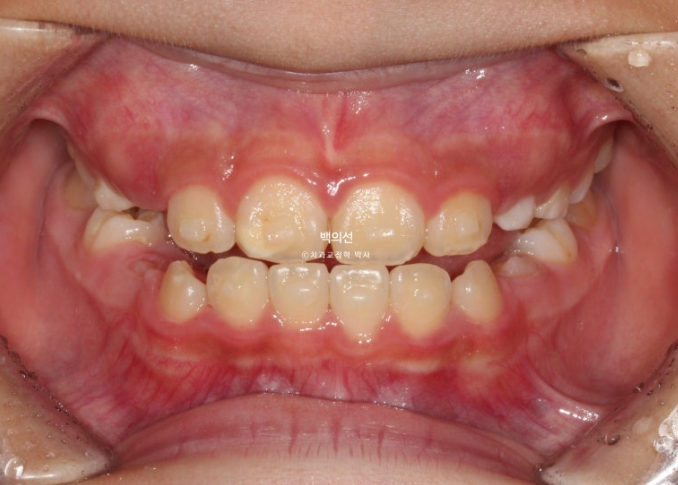

24년 10월부터 25년 3월까지, 16개 추가장치를 다 낀 후 모습입니다.

25.03

턱의 위치는 6개월간 자연스럽게 잘 유지가 되었고 치료를 마무리 합니다.

중심선도 아주 잘 맞습니다.

교합은 좋고 이제 막 첫번째 작은어금니가 맹출중입니다.

23.12~25.03

치료 결과가 좋은 만큼 유지장치도 성인에 준하게 송곳니부터 송곳니까지 들어갑니다.

소아교정이지만 결과가 이정도 되면 나중에 커서 2차교정을 안해도 됩니다.